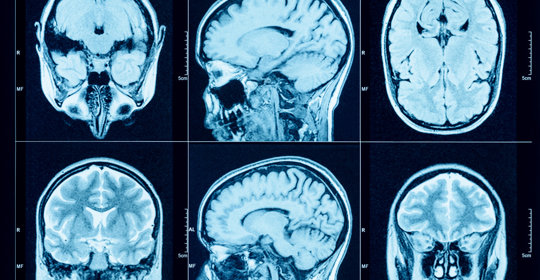

腦幹梗塞:前兆、原因、後遺症及治療方法

腦實質浸潤:症狀與治療

腦實質浸潤:症狀與處理

腦幹梗塞:診斷與治療

腔隙性腦梗塞:症狀、診斷與治療

腦實質的浸潤:病因與治療方法

腦幹梗塞:原因、症狀及治療方法

腦幹梗塞:症狀、恢復及預防